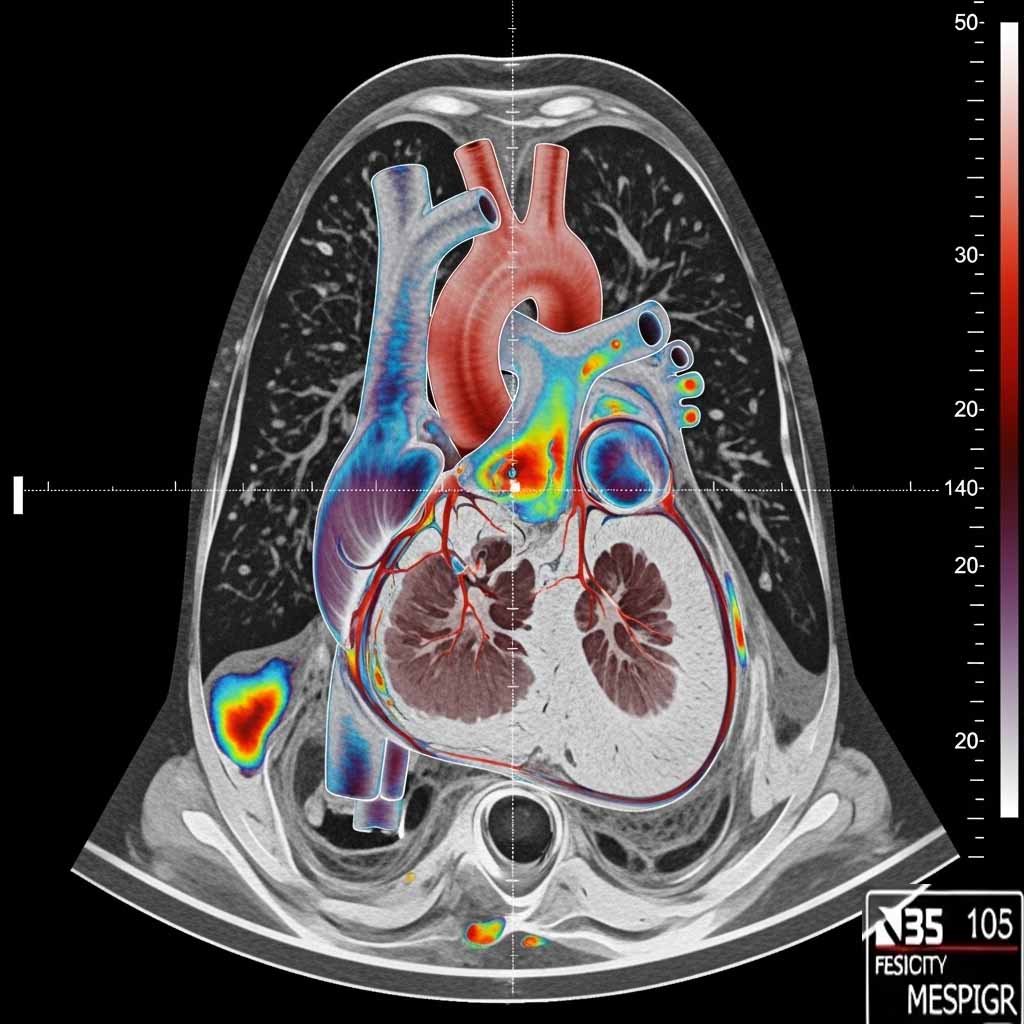

در مرکز اسکن هستهای مهرشاد، اسکن هستهای قلب با بالاترین دقت و مطابق با جدیدترین استانداردهای پزشکی انجام میشود.

این روش پیشرفته برای بررسی جریان خون قلب، تشخیص گرفتگی عروق کرونر و ارزیابی عملکرد بطنها کاربرد دارد.

ما با استفاده از رادیوداروهای استاندارد و دستگاه گاما کمرا، تصاویری دقیق از فعالیت قلب شما تهیه میکنیم.

اسکن قلب در دو مرحله انجام میشود تا عملکرد قلب در شرایط مختلف بررسی گردد.